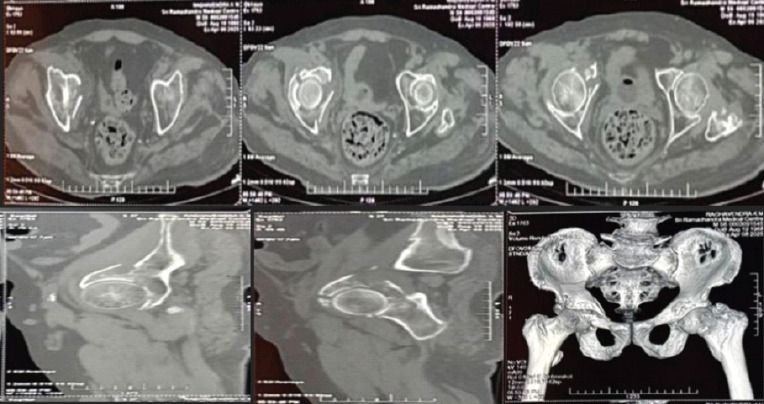

Case report: A 63-year-old male presented with right hip pain and inability to bear weight after a standing-height fall. Imaging revealed a comminuted right acetabular fracture with superomedial dome impaction, quadrilateral plate involvement, and central subluxation. The patient underwent open reduction and internal fixation through a modified Stoppa approach using a suprapectineal plate. Postoperatively, an accelerated rehabilitation protocol was implemented, progressing to full weight-bearing by 6 weeks with radiographic evidence of union.